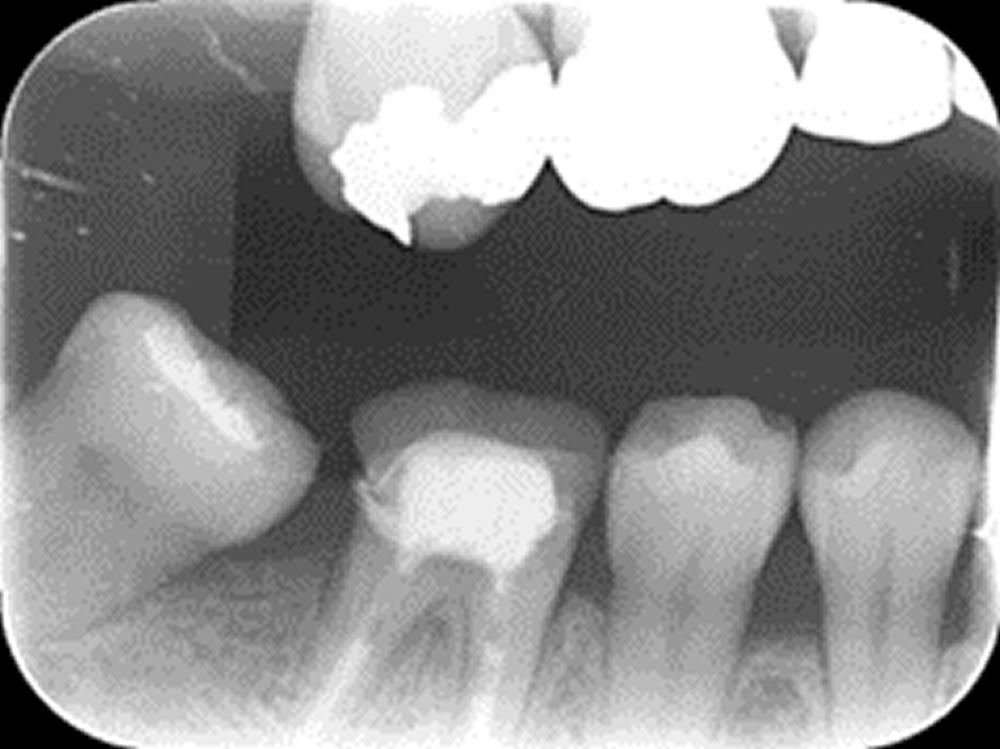

つめ物が外れた歯を虫歯治療後にセラミックで修復した症例

つめ物が外れた歯を虫歯治療後にセラミックで修復した症例 こちらの患者さまは、右上前から数えて4番目の詰め物が取れてしまい、来院されました。 口腔内を確認すると、右上5番目にもむし歯の進行を確認しました。 神経のある歯な […]